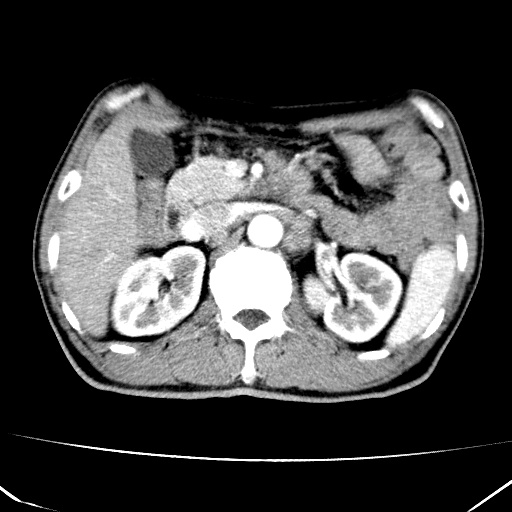

标题: CT17975:请求会诊。男、57岁。上腹部胀痛2天。临床诊断:糜 [打印本页]

标题: CT17975:请求会诊。男、57岁。上腹部胀痛2天。临床诊断:糜

肝脏多发类圆形低密度影,考虑肝脏转移瘤,肝胃韧带一淋巴结肿大,原发?胃癌?

考虑胃癌并肝脏及腹膜后淋巴结转移;不排除淋巴瘤。

肝内转移瘤,腹腔及腹膜后淋巴结转移。